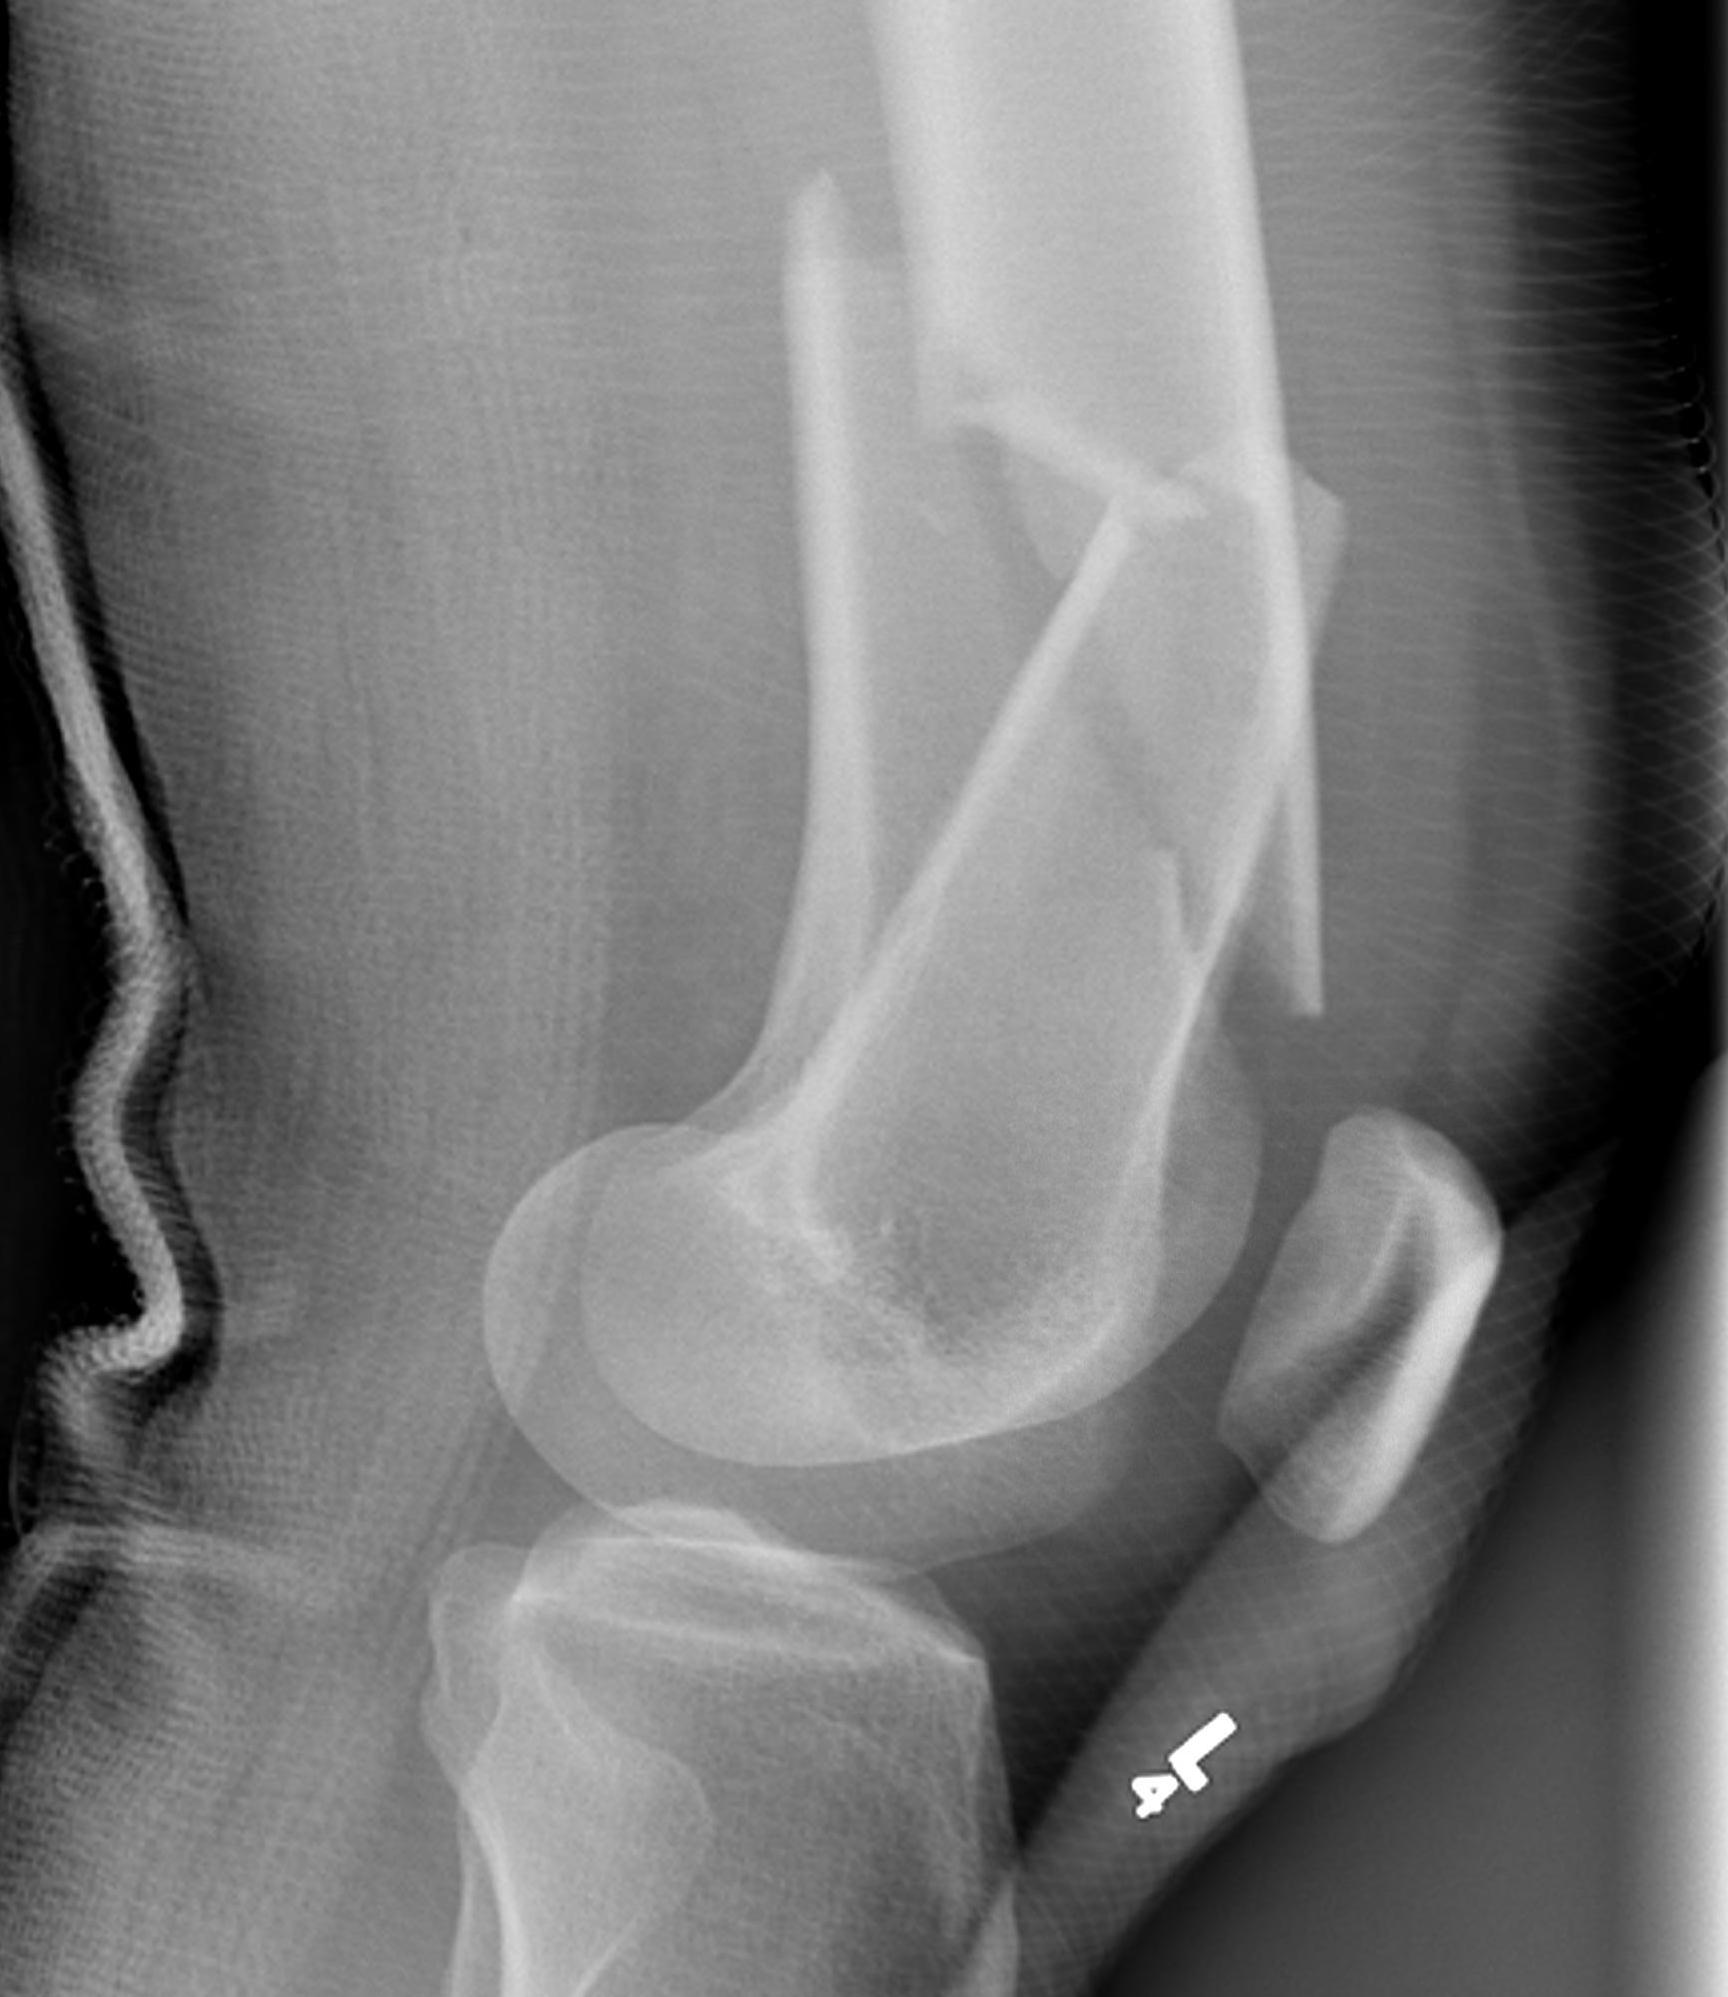

AO Type A: Supracondylar / Extra-condylar

Xray

Options

Lateral plate

Retrograde IM nail